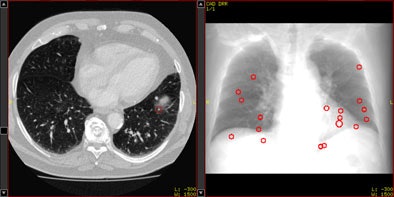

| Above, axial CT image in standard-dose CT (SD-CT) showing a nodule in juxtadiaphragmatic location missed by CAD-1. Above right, CAD markers resulting from the analysis of the SD-CT data presented in a coronal view. Below, CAD analysis of the ultralow-dose CT (ULD-CT) data resulted in automated detection of the corresponding nodule in the left lower lobe. On the right, CAD markers resulting from the analysis of the ULD-CT data. All images courtesy of Dr. Valentina Romano. |

The group compared the results of CAD analysis by assessing detection sensitivity and false-positive detections with ultralow-dose CT (ULD-CT) and standard-dose CT (SD-CT) protocols. Data were collected on 26 patients with known lung cancers.

CT images were consecutively acquired at 5 mAs (ULD-CT) and 75 mAs (SD-CT) with 120 kV tube voltage and 1-mm slice thickness. Images were examined using a soft-tissue kernel as recommended by the manufacturers.

The sensitivity results for both systems did not decline significantly for standard-dose protocols versus low-dose settings: for SD-CT and ULD-CT, respectively, the sensitivity for detecting nodules 4 mm and larger was 72% and 73% for the CAD-1 application and 62% and 56% for CAD-2.